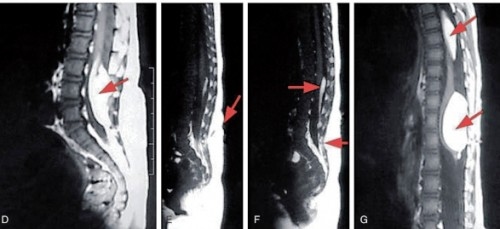

- Đau lưng về đêm có thể là triệu chứng của khối u cột sống: Đây là một khối u nguyên phát, bắt nguồn từ cột sống hoặc có thể do di căn.

- Hiện tượng đau lưng khi ngủ cũng là triệu chứng của bệnh nhiễm trùng xương cột sống (viêm tủy xương) và viêm cột sống dính khớp.